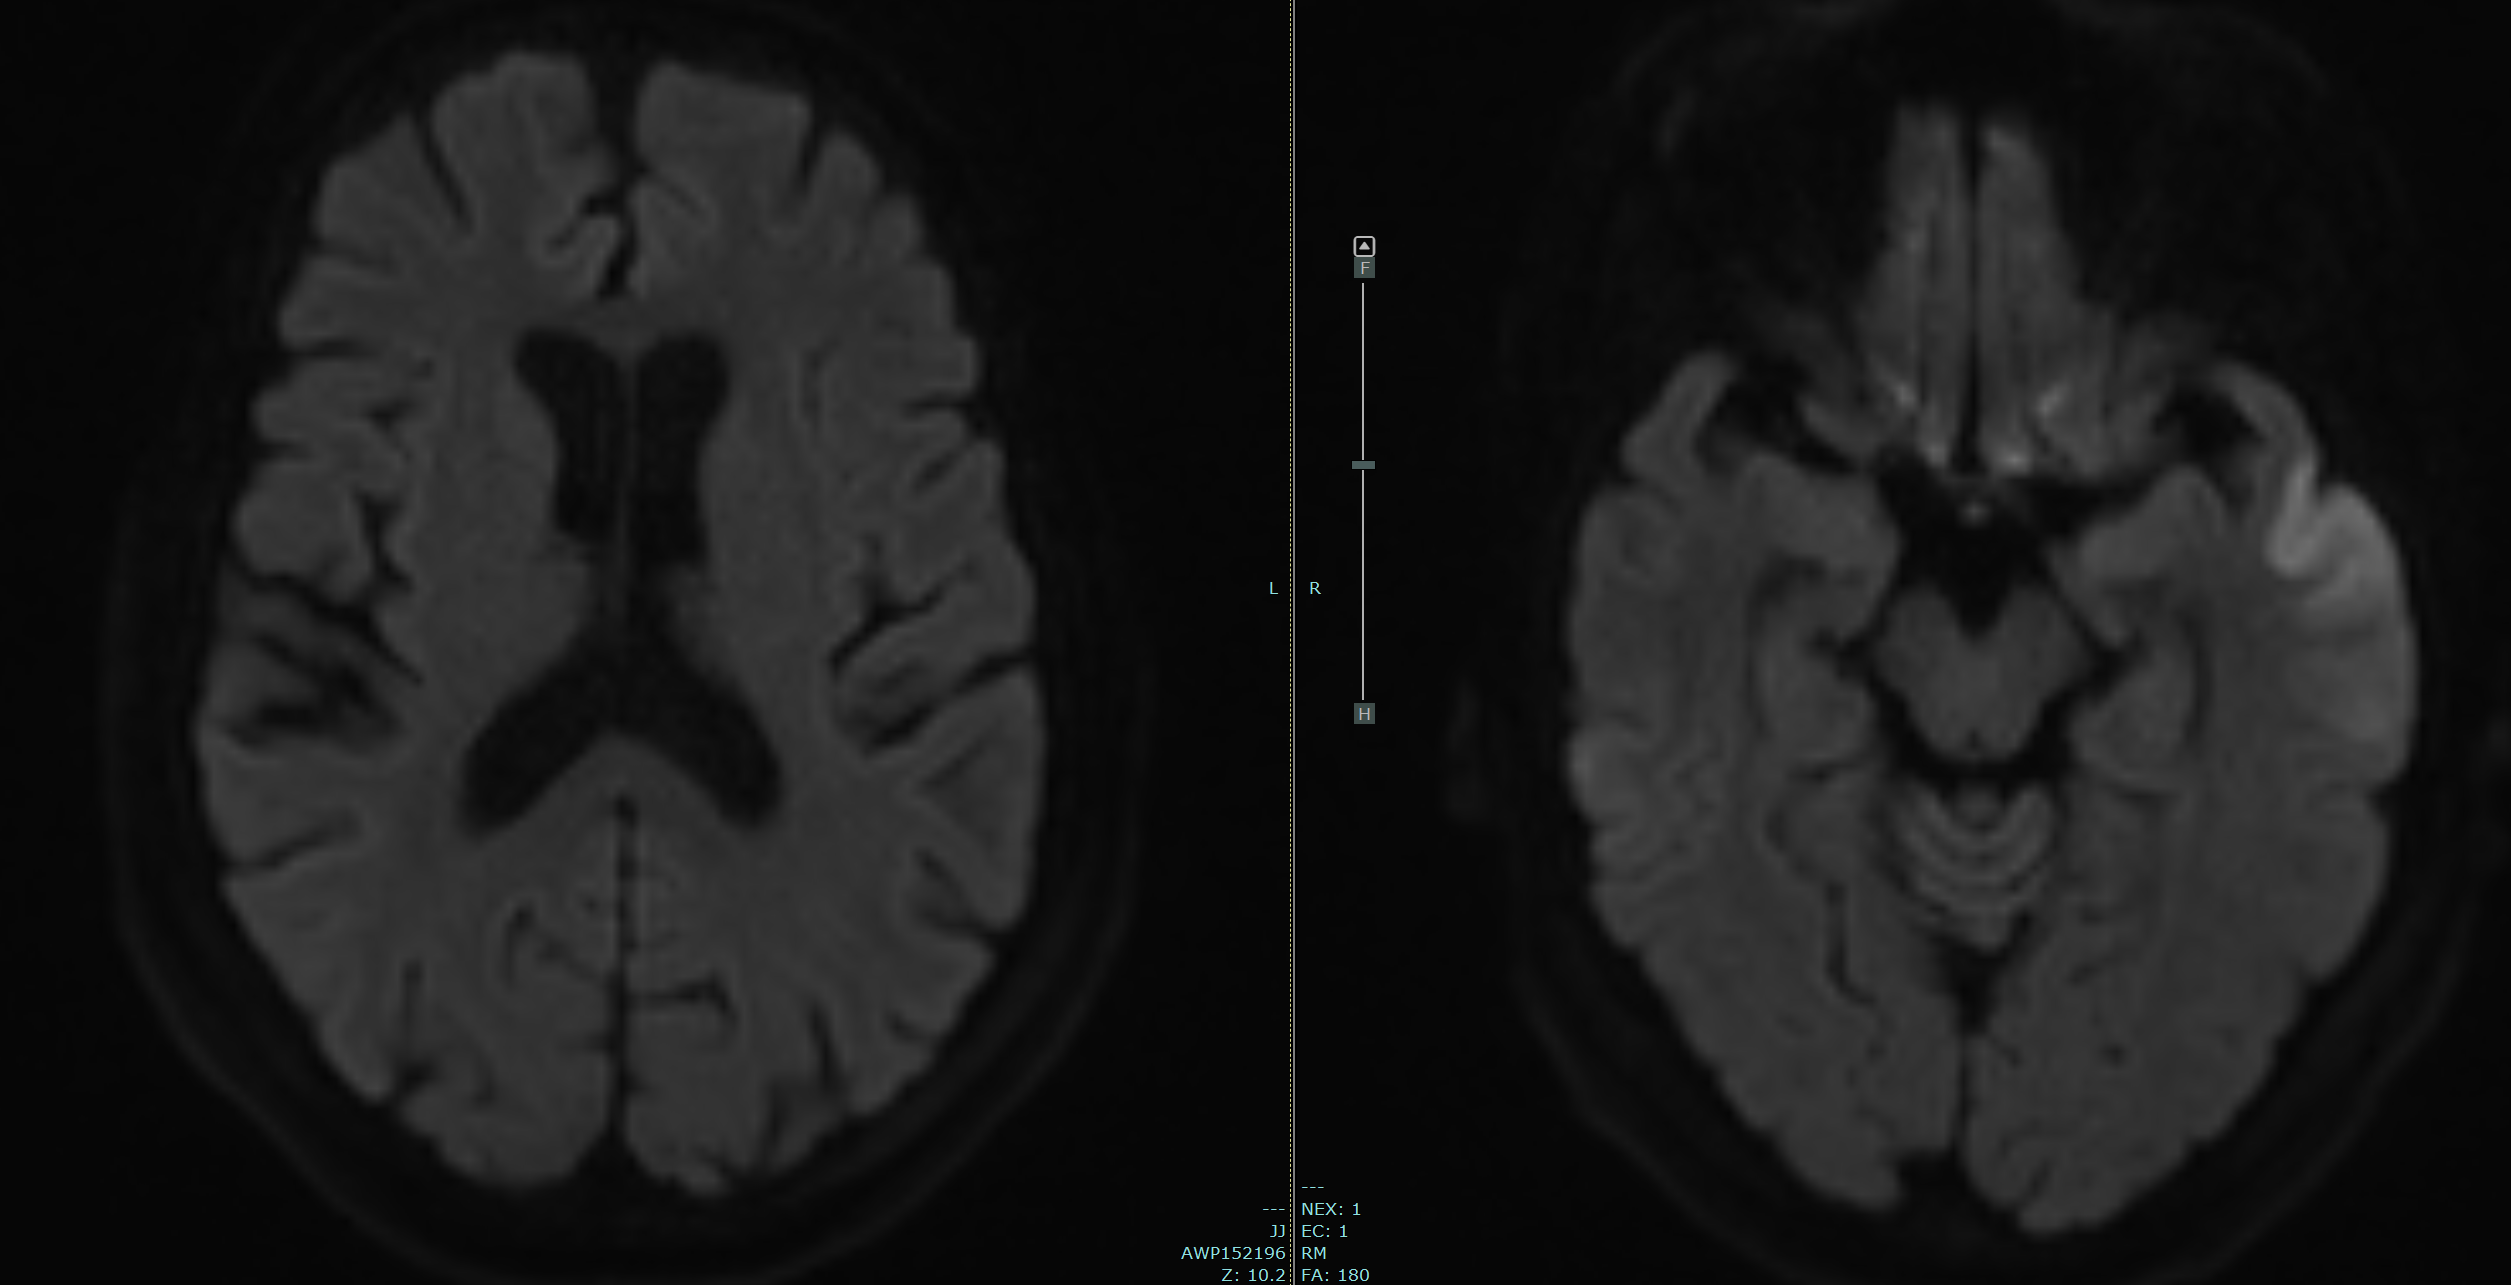

MRI

629.8 kb

PNG